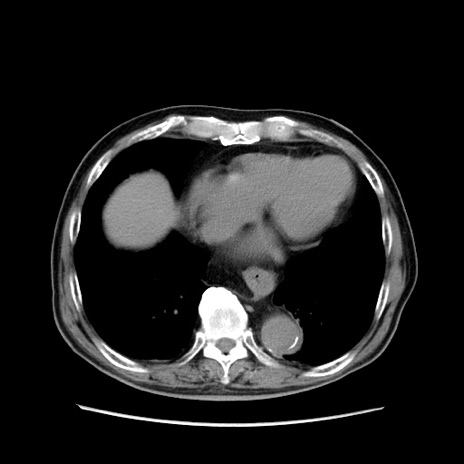

症例24(横断像)

【症例】80歳代男性

【主訴】左側腹部痛、嘔吐

【現病歴】本日早朝より左腹部に痛みあり。昼頃嘔吐認めたため、救急要請。

【既往歴】直腸癌(Mile手術)、胆摘

【身体所見】意識清明、BT 35.9℃、BP 221/93mmHg、SpO2 97%(RA) 、腹部:左ストーマ周囲に限局性の腹部膨隆あり。 膨隆部自発痛・圧痛あり・軟。

【データ】WBC 7700、CRP 0.09